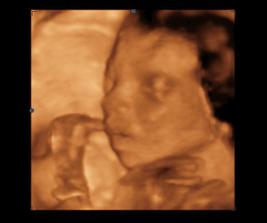

14.1.2010 3D ultrazvuk podľa PM presne 13tt+0 , na drobčeka sa bol pozrieť 1.krat aj tatinko, bolo to krásne 🙂 /////